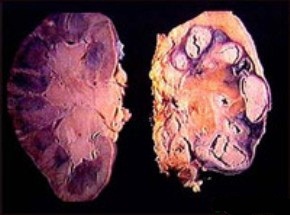

туберкулез почки - фотоТуберкулез почек – инфекционное поражение, почечной паренхимы, которое вызывается специфическим микроорганизмом: микобактерия туберкулеза (Mycobacteriumtuberculosis, Палочка Коха, МБТ). Поражение почек занимает 1 место среди всех внелёгочных органных форм туберкулеза, и наблюдается в 30-40% легочных поражений.

• Кавернозный туберкулез почки (каверна - полость) – слияние нескольких деструктивных очагов, формирование фиброзной капсулы, поражение чашечно-лоханочной системы с выходом казеозных масс в просвет почки – приводит к формированию одной или нескольких полостей почки.

• Фиброзно-кавернозный туберкулез почки – иногда на фоне туберкулезного папиллита преимущественно поражается шейка одной или нескольких чашечек, они сдавливаются и облитерируются (зарастают). При этом развивается деструктивно-гнойная полость, состоящая из зоны разрушенного сосочка и ретенционно измененной (растянутой) чашечки. При этом исчезает возможность оттока содержимого полости.